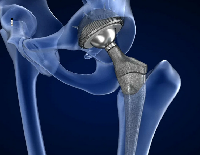

В случае перелома шейки бедра компания МосРентген Центр госпитализирует в Склиф для эндопротезирования.